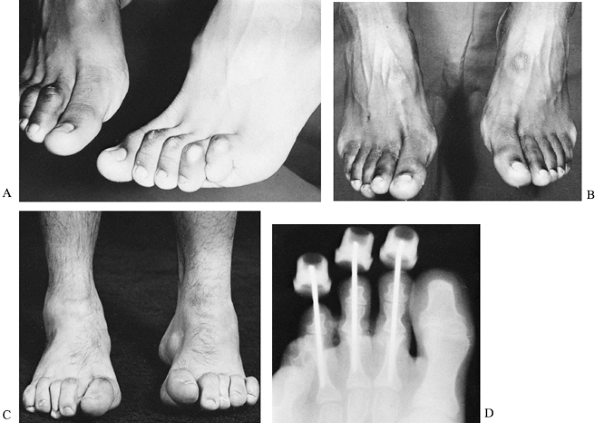

|

Figure 178.15. Pre- (A) and postoperative radiographs of a cavovarus foot treated by a triple arthrodesis (B).

indicates satisfactory results, but there is a high incidence of

radiologic ankle and midfoot arthritis (289,364).

A study of triple arthrodesis using force plate analysis demonstrates

increased midfoot load bearing and load concentration under the

metatarsal heads (318). The incidence of

pseudarthrosis, typically in the talonavicular joint, is reported to

occur up to 25% of the time. This can be symptomatic and require